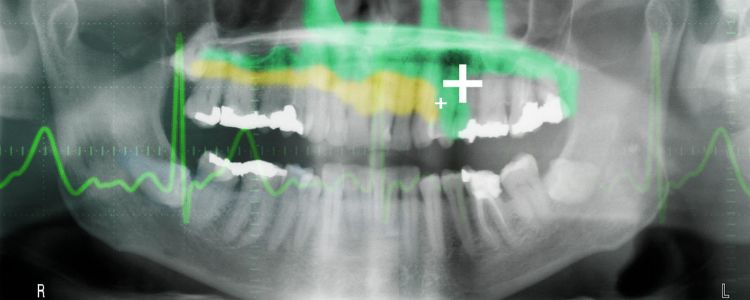

Ніхто при здоровому глузді не буде коли-небудь розраховувати на заповнення у стоматолога. Чому наші зуби не можуть виправити себе? Може бути, вони можуть. Зрештою, вчені з Ноттінгемського університету і Гарвардського університету, можливо, зробила революцію, як ми дивимося на лікування стоматологічних проблем. Їх регенеративні зубні пломби дозволяють зуби лікувати себе, потенційно усуваючи необхідність в пронизливо буріння притаманна кореневих каналів.

Зуб закладних робіт шляхом стимуляції стовбурових клітин для стимуляції росту дентину. Це кісткова матеріал, який становить більшу частину зуба. Таким чином, пацієнти можуть ефективно відростити зуби пошкоджені через стоматологічних захворювань. У порівнянні з існуючими методами, що застосовуються для лікування карієсу, це може здатися великою будь-якого зі страхом стоматолога.

Крім меншою травматичного досвіду в кріслі, є багато переваг цього типу стоматології. "Існуючі зубні пломби є токсичними для клітин і, отже, несумісні з целюлозної тканини всередині зуба," сказав Адам Celiz, науковий співробітник з університету Ноттінгема. "У випадках стоматологічних захворювань пульпи і пошкодження кореневого каналу зазвичай виконується для видалення інфікованих тканин."

Celiz описує процес, "Ми розробили синтетичні біоматеріали, які можуть бути використані так само, зубних пломб, але можуть бути поміщені в безпосередньому контакті з целюлозної тканини, щоб стимулювати нативную популяції стовбурових клітин для відновлення і регенерації тканини пульпи і навколишнього дентину."